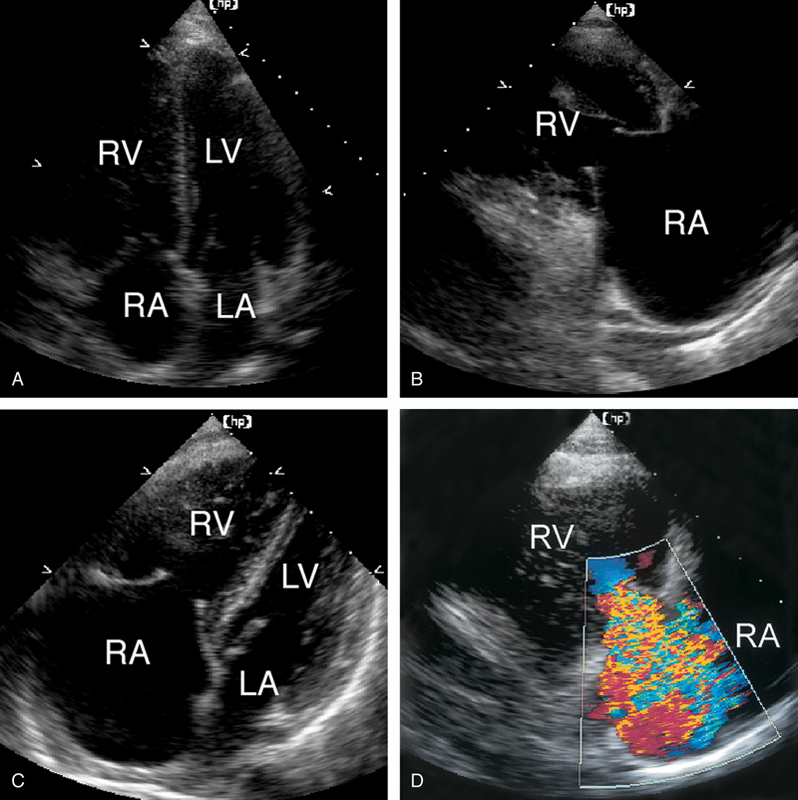

فحوصات تشخيصية لبعض امراض القلب والشرايين التاجية